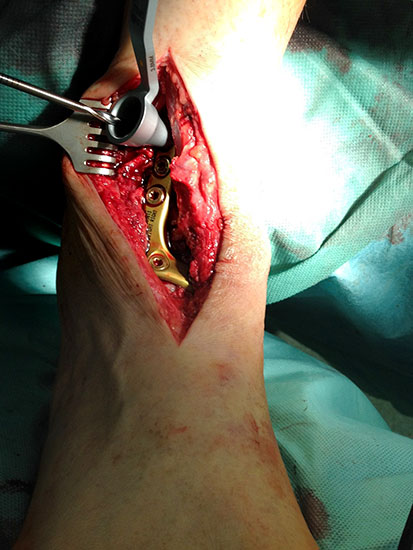

Kapsulotomie und Synovialektomie. Entknorpeln der Gelenkflächen bis knapp in den subchondralen Raum. Mit Kuretten, gebogenem Meißel, oszillierender Säge und/oder hochtourigen Fräsen Entknorpeln der tibialen, fibularen und tibialen Gelenkfläche und Abtragung von knöchernen Anbauten (Abb. 3). Die Präparation entlang der vorgegebenen Kontur des Talus und der Tibia bietet den Vorteil eines geringeren Längenverlustes gegenüber geraden Sägeschnitten. Der anteriore Zugang bietet insbesondere bei Verwendung eines Arthrodese Spreizers eine gute Übersicht in die anterioren Kompartimente. Der antero-laterale transfibuläre Zugang ergibt eine hervorragende Übersicht, allerdings nicht auf das mediale tibio-talare Kompatiment.

Abbildung 3